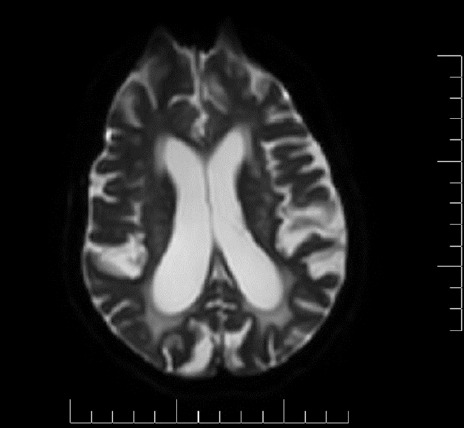

Alzheimer disease (AD) is the most common cause of dementia worldwide. Its clinical manifestations include a progressive loss of memory and other cognitive domains, as well as brain atrophy. An elevated homocysteine level (>15 µmol/L), known as hyperhomocysteinemia, is also an attributing risk factor for AD, vascular pathologies, and brain atrophy. Neuroimaging studies including T2-weighted magnetic resonance imaging scans revealed white matter hyperintensities in the periventricular and deep white matter, enlarged ventricles, widened sulci, and decreased white matter mass, which are features of aging, as well as cerebrovascular changes. This case series investigated changes in biochemical marker levels including serum homocysteine, folate, and vitamin B12, and the degree of atrophic variations in cortical-subcortical white matter in AD. The present study hypothesized that serum homocysteine levels might be used as a surrogate marker to screen for AD at an earlier stage.

Abstract Image

阿尔茨海默病(AD)是全球最常见的痴呆症病因。其临床表现包括记忆力和其他认知能力的逐渐丧失,以及脑萎缩。同型半胱氨酸水平升高(>15 µmol/L),即高同型半胱氨酸血症,也是导致老年痴呆症、血管病变和脑萎缩的一个危险因素。包括 T2 加权磁共振成像(MRI)扫描在内的神经影像学研究显示,脑室周围和深部白质中存在白质高密度(WMH),脑室扩大,脑沟增宽,白质质量减少,这些都是衰老以及脑血管变化的特征。本系列病例研究了 AD 患者血清同型半胱氨酸、叶酸和维生素 B12 等生化标志物水平的变化,以及皮质-皮质下白质萎缩变异的程度。本研究假设,大脑中的血清同型半胱氨酸水平可作为一种替代标志物,用于早期筛查 AD。